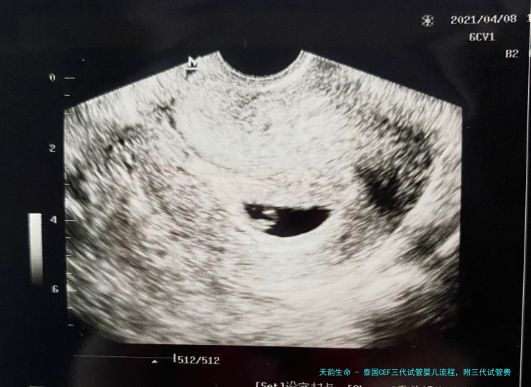

要是您的身体条件适合,则进入促排卵治疗阶段,医生会根据您的详细情况制定个性化的方案,通过口服药物或注射药物来刺激卵巢发育和成熟卵泡产出。同一时刻,男性需要提精子液标本进行检查和保存。在促排卵当天,我们将采用超声引导下微创手术取出成熟卵子,并与老公的精子结合培养胚胎。

三代试管婴儿技术最大的长处在于可以对胚胎进行基因筛选,抉择健康精良的胚胎移植到女性子宫内,进而提升成功率和压低患有遗传病症的风险。在胚胎移植后,我们将紧密察看您的身体状况,并准时进行血检和B超监测,确保妊娠顺利进行。

3. 妊娠监测:移植后,医院会定期进行B超检查、抽血检测等项目,监测胚胎着床和发育情况,并及时提供相应的治疗和指导。